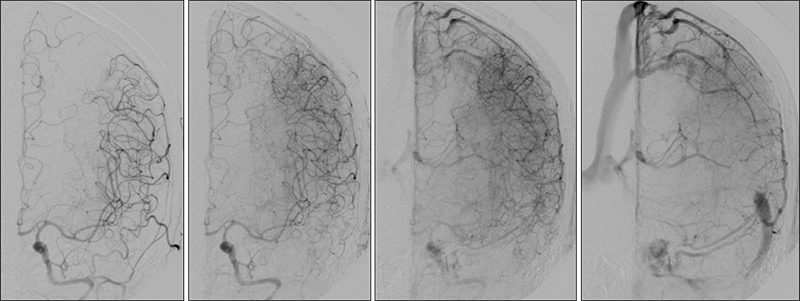

Εικόνα 10: Τοποθέτηση του εγγύς συστήματος προστασίας MOMA με διάταση του περιφερικού μπαλονιού στην αρχή της αριστερής έσω καρωτίδος.

Εικόνα 11: Αποκατάσταση της στενώσεως του αριστερού καρωτιδικού βολβού με  τοποθέτηση stent τύπου closed-cell.

Εικόνα 12 και 13: Κατά την ενδοκράνια προσθιοπίσθια και πλάγια προβολή της αριστερής κοινής καρωτίδος μετά την επέμβαση, παρατηρείται σημαντική αιμοδυναμική βελτίωση με αναστροφή της ροής στην αριστερή πρόσθια εγκεφαλική αρτηρία που είναι πλέον ομόδρομη.